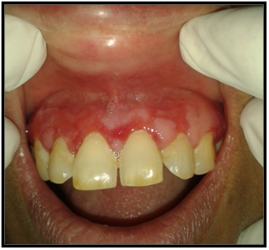

On intraoral examination, diffuse lesions in the form of erythematous areas were seen interspersed within white keratotic areas present all over the facial aspect of gingiva (Figure 2) and more posteriorly on the buccal mucosae bilaterally (Figure 3). Left buccal mucosa showed a white erythematous patch measuring approximately 2x2.5cms extending anteroposteriorly from the area adjacent to mandibular first molar to the retro molar pad area and superior inferiorly from the line of occlusion to the upper and lower lingual vestibule. White radiating striae (wickhamstriae) were present with an interspersed erythematous patch. Right buccal mucosa showed a more extensive lesion measuring approximately 2.5x3cms extending anteroposteriorly from the region adjacent to mandibular canine to the retromolar pad area and superioinferiorly from the upper gingiva buccal sulcus to the lower gingivobuccal sulcus and the alveolar mucosa. Borders of the lesion appear irregular and ill defined. On palpation, the lesions appeared to be tender. The surface of the lesions were rough and non scrapable with no induration noted.

Figure 3 The lesion on the facial gingiva.

On hard tissue examination, all complements of teeth were present in all the 4 quadrants except 46, with generalized attrition and a thick band of local deposits of plaque and calculus. Mobility was absent and occlusion was angle’s class I molar relationship bilaterally. Few carious teeth were also elicited which showed no symptoms like pain, swelling or tenderness. Based on the patient’s history and clinical findings, the lesion was provisionally diagnosed as Oral Erosive Lichen Planus on facial gingivae and buccal mucosae bilaterally.